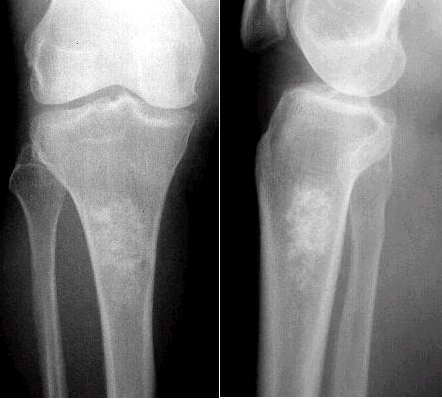

大家看看下面这例骨梗死吧!(资料来源:中国医学影像网站,每日病例)

男性 42岁,右膝疼痛3月。

x线表现:右膝关节正位及侧位片显示右胫骨上段骨髓腔内片状高密度影,边缘清楚。

最后诊断:右股骨下段骨梗死。